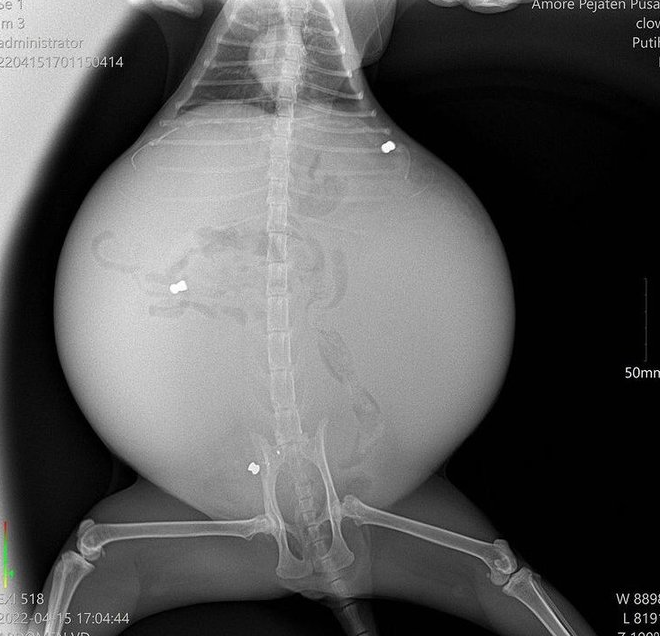

Dalam satu video yang tular di media sosi4l beberapa hari lepas menunjukkan seekor kucing berwarna putih bertompok oren mengalami masalah perut yang membesar hingga kelihatan meng3rikan. Lebih memilukan, haiwan berkenaan juga dilihat mengalami kesukaran untuk berjalan. Pada awalnya, tiada sesiapa pun tahu punca yang menyebabkannya menderita sedemikian rupa. Ini kerana terdapat 3 das peIuru di dalam perutnya.

Kucing ini akhirnya berjaya diselamatkan melalui pemb3dahan. Ketika nanah dikeluarkan daripada perutnya, doktor turut menemui 3 butir peIuru yang dikesan lebih awal melalui imbasan x-ray.

Dibawah adalah gambar xray PeIuru yang masuk dalam perutnya.